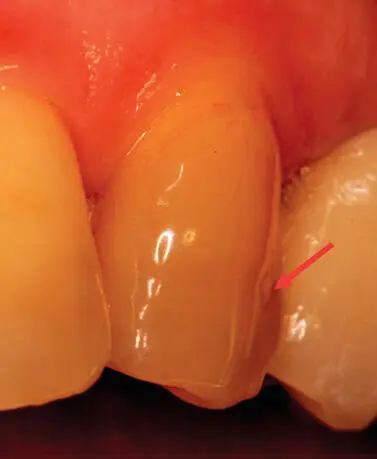

Por lo general, clínicamente las manchas blancas se corresponden con lesiones restringidas solo al esmalte, mientras que las manchas oscuras (generalmente marrones) se corresponden con las que llegan a la unión amelodentinaria; las cavitadas se corresponden a lesiones en dentina (Fig. 4.3) (Da Silva et al., 2008).

Figura 4.3.De izquierda a derecha, imágenes ubicadas en proximal: correspondientes a mancha blanca, lesión remineralizada y lesión cavitada.